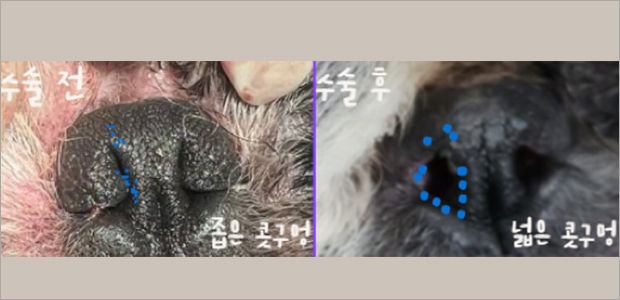

단두종 증후군 수술

단두종 증후군은 호흡에 직접적인 연관이 있기 때문에 풍부한 수술 경험이 매우 중요합니다.

서울대학교 동물병원 팀장으로 근무한 이누리 부원장은 숙련된 기술로 단두종 증후군 수술을 진행해 삶의 질을 개선합니다.

연구개 및 후두허탈, 후두부종, 기관저형성 등 환자 호흡상태를 정확히 평가하여 환자 맞춤 수술계획을 세우게 됩니다.

비공협착 교정술 케이스